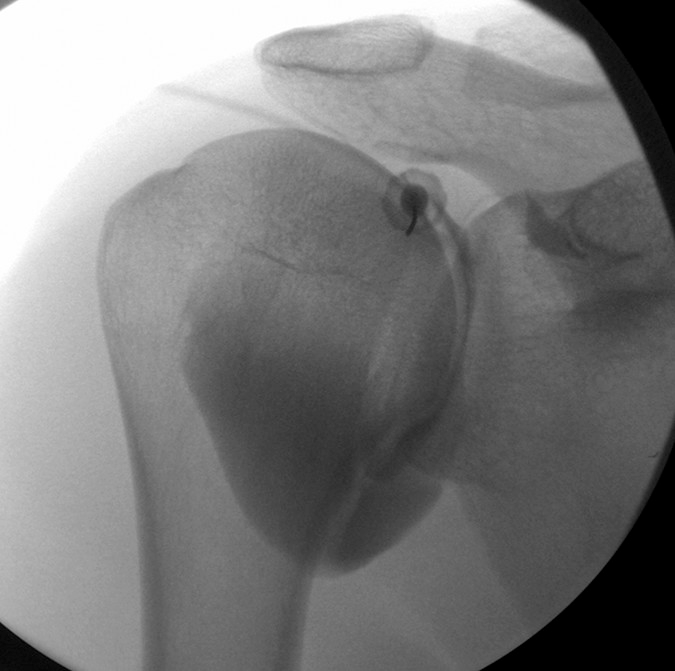

Shoulder¶

- Shoulder is externally rotated to move biceps tendon out of the way

- Target is superior medial quadrant of humeral head, between 1- and 2-o'clock positions for right shoulder and 3–5 mm in from edge of cortex.